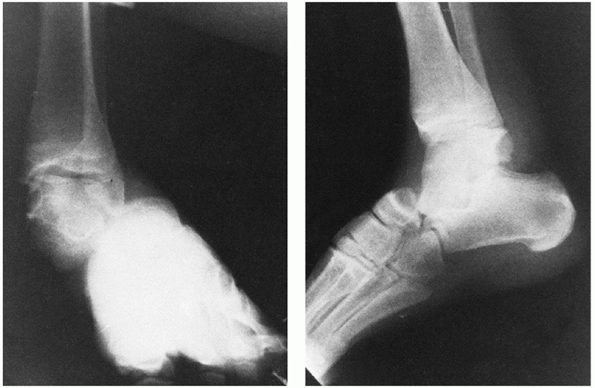

Tibiocalcaneal arthrodesis and the Blair or modified Blair fusion have

been found effective. Blair12

described a technique of ankle fusion in 1943 specifically designed to

treat osteonecrosis of the talus. He recommended excision of the

avascular talar body and placement of a sliding corticocancellous graft

from the anterior distal tibia into the residual, viable talar head and

neck (Fig. 58-18). Modifications of this

technique include screw fixation of the sliding anterior distal tibial

graft, suggested by Lionberger et al.,115 and retention of the talar body. Authors such as Morris et al.137 and Dennis and Toulos37

have reviewed case series and recommend the modified Blair fusion as a

satisfactory reconstructive treatment after severe talar injuries.

Note the space left by removal of the talar body. (Blair HC. Comminuted fractures and fracture dislocations of the body of the astragalus: operative treatment. Am J Surg 1943;59:38.) D,E. Radiographs demonstrate a healed modified Blair fusion 2 years following a type III talar neck fracture with the sliding graft incorporated. The talar body has been retained and remains sclerotic, but appears to be healed to the distal tibia. |